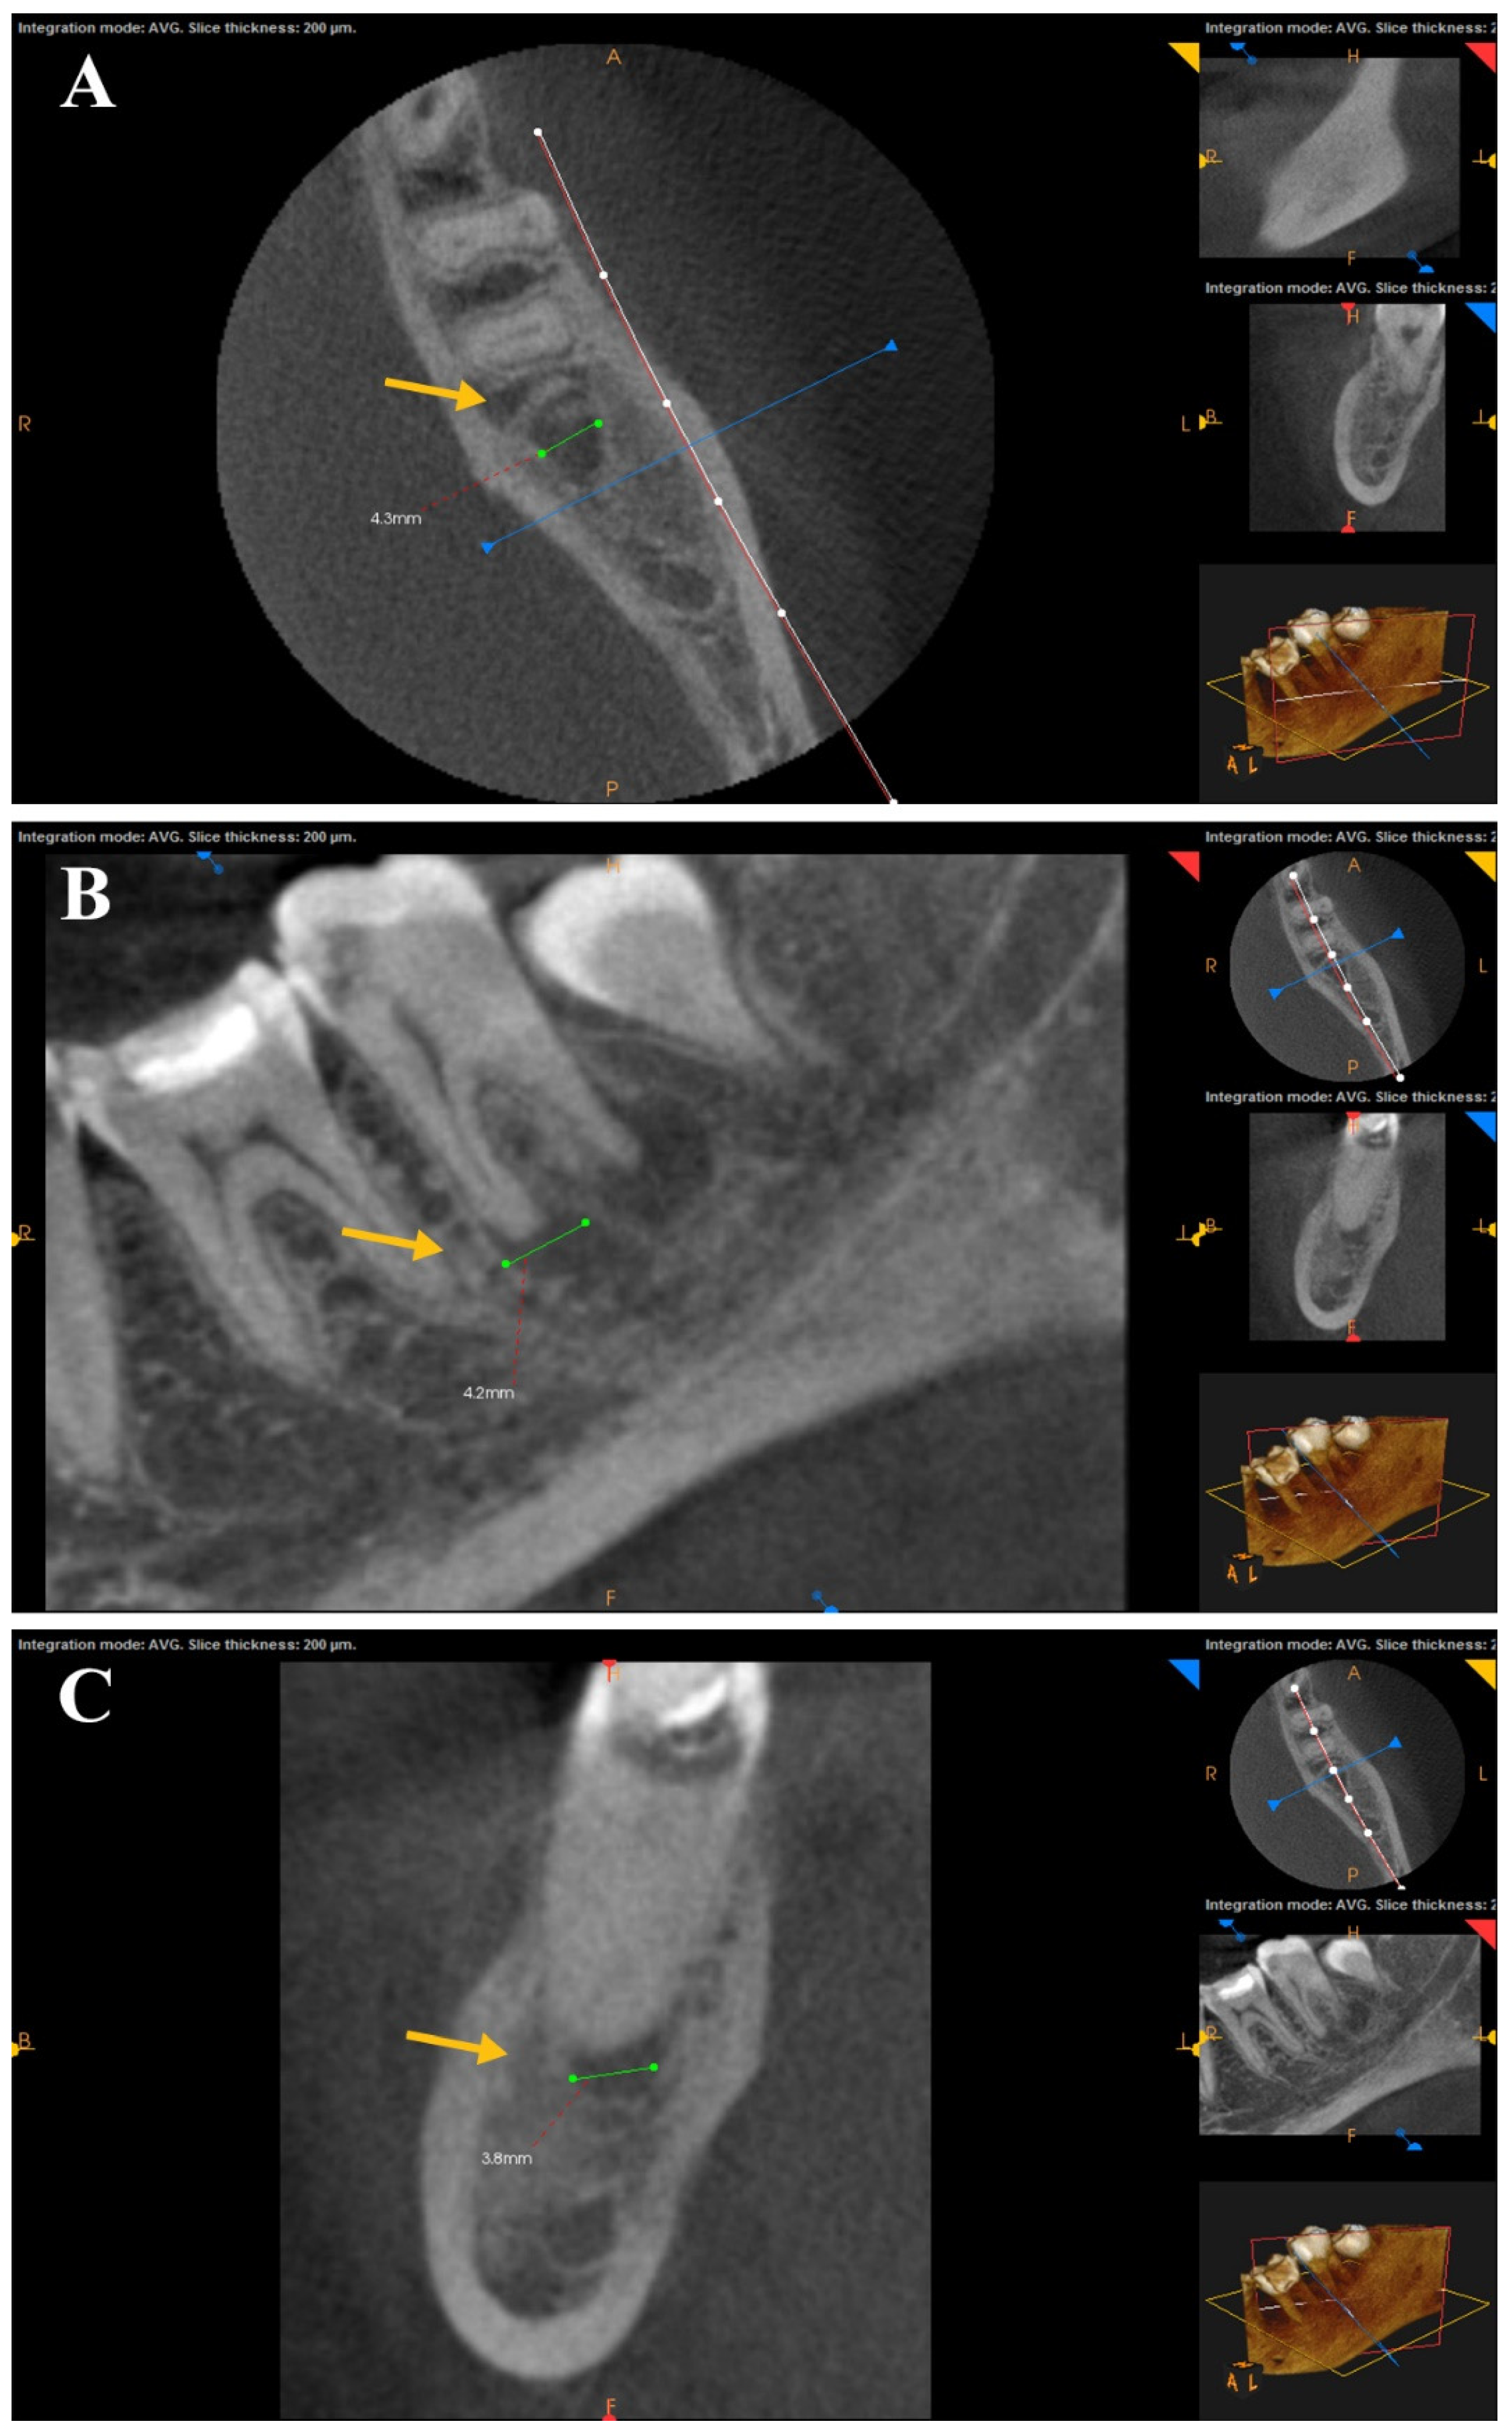

A statistical comparison of preoperative periapical lesions was performed using CBCT images across the three study groups before root canal treatment. There was no significant difference between the tested groups in pre-operative CBCT images. The periapical lesions were statistically compared for each group before RCT and after one year. A Wilcoxon Signed-Rank Test showed a statistically significant difference (p < 0.05) for the mean ranks before RCT and after one year for each group. CBCT scans for each group showed healing of the periapical lesions after one year of follow-up. No statistical significance was found in post-operative CBCT images between the three tested groups. The difference between the healing of periapical lesions after canal preparation with the rotary SS Tornado system was nonsignificant compared to WaveOne and OneShape rotary Ni-Ti single-file systems. Figure 3, Figure 4 and Figure 5 show CBCT images of preapical lesions before root canal preparation and after one year for the three groups. Complete healing was detected in the axial, sagittal, and coronal views of the three file systems.

Figure 5. CBCT scans of the OneShape file group before (ac) and after one year (AC). Complete healing was detected in the axial, sagittal, and coronal views (arrows, the white is “before” and the yellow is “after” treatment).